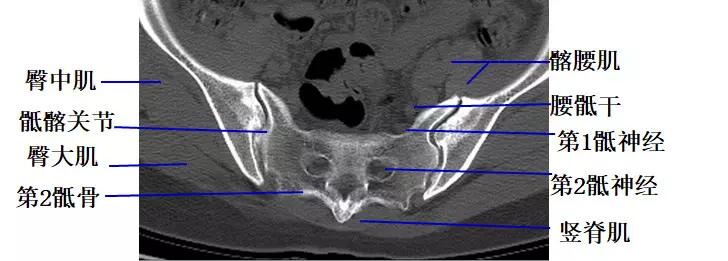

经第2骶椎体的横断层面(CT)